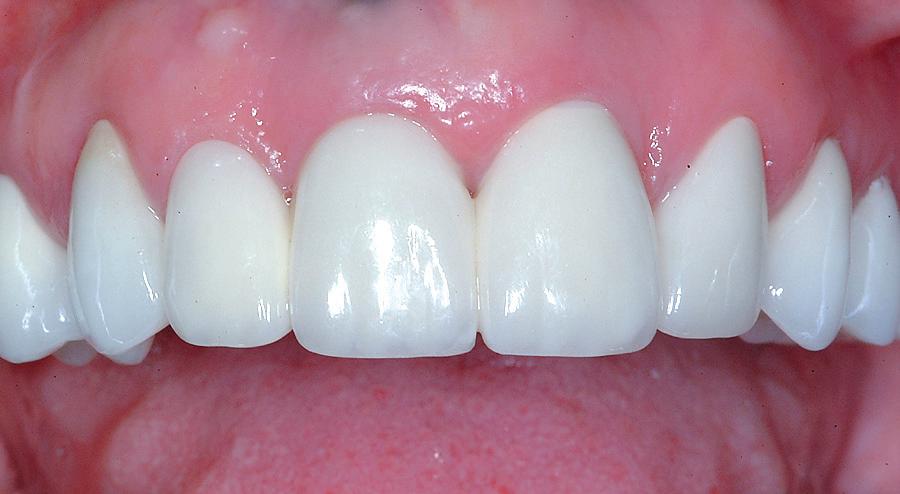

La controlul de două luni, nu au fost raportate simptome, nu s-a obiectivat radiologic nicio leziune periapicală, iar examenul clinic a

demonstrat o vitalitate în limite normale (fig. 9-10). Prin urmare, s-a decis efectuarea restaurării definitive, păstrând Biodentine™ ca bază definitivă.

Figurile:

10. Restaurarea Biodentine™ după 2 luni.

16. Restaurarea imediat după finalizare.

17. Situația clinică după finisare și lustruire.